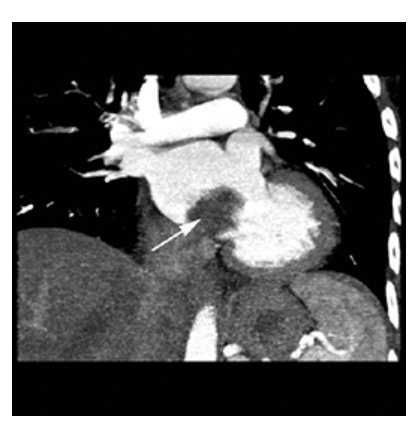

Atrial Myxoma. Contrast-enhanced axial CT shows a round filling defect/mass in the left atrium consistent with a myxoma (arrow).

Atrial Myxoma. Contrast-enhanced coronal MPR CT shows a round filling defect/mass in the left atrium consistent with a myxoma (arrow).

Atrial Myxoma. Contrast-enhanced sagittal MPR CT shows a round filling defect/mass in the left atrium consistent with a myxoma (arrow).